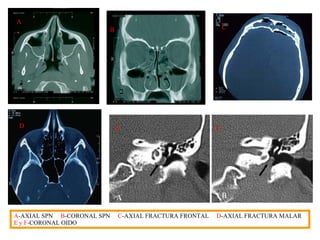

EL ESTUDIO Para comenzar el estudio necesitamos identificar, no solo al paciente, sino también la zona anatómica que queremos estudiar. Para todo esto el radiólogo nos dará la programación, es decir, la zona correcta que tenemos que cortar, los grosores e intervalos de corte, la administración o no del contraste y el tipo. Una vez que nos aseguramos que coincidan tanto los datos del paciente como el estudio requerido, pasamos a la colocación del paciente en la camilla. Le explicamos lo que vamos s hacer e introducimos los datos en la consola de operaciones: -Numero de identificación del estudio  -Sexo -El del paciente  -Procedencia -Apellido y nombres  -Tipo de estudio -Edad  -Características y parámetros del estudio  PLANOS El tomógrafo va a realizar cortes  axiales  y por medio de la angulacion del gantry y determinadas posiciones del paciente, también cortes  coronales . Los planos de corte mas comúnmente utilizados, lo s cuales en algún caso , pueden variar son: CRÁNEO:  AXIAL - SILLA TURCA:  CORONAL - SENOS PARANASALES:  AXIAL o CORONAL ORBITAS:  AXIAL o CORONAL - PEÑASCOS:  IGUAL - CAVUN, LARINGE:  AXIAL TORAX:  AXIAL - COL CERVICAL:  AXIAL - COL DORSAL:  AXIAL-  ABDOMEN:  AXIAL COL LUMBAR:  AXIAL - PELVIS:  AXIAL - CADERAS:  AXIAL.

A B B C D E F A -AXIAL SPN   B -CORONAL SPN   C -AXIAL FRACTURA FRONTAL   D -AXIAL FRACTURA MALAR  E y F -CORONAL OIDO